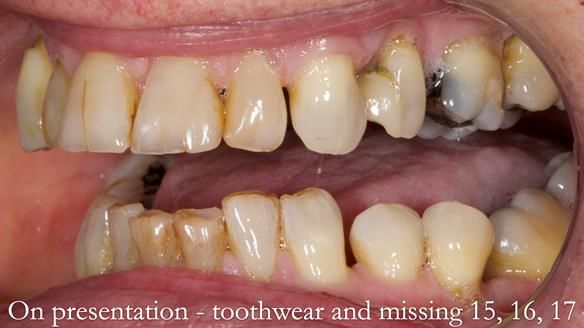

Welcome to Newsletter 64. I'll walk you through the process of providing a Mk 2 metal-based partial denture (RPD), for Ian a retired Veterinary Surgeon aged 78. The RPD was made at an increased vertical dimension and acted as an occlusal stabilisation splint - reducing the wear and bite force on the remaining natural teeth.

Ian was referred to me by his general dentist.